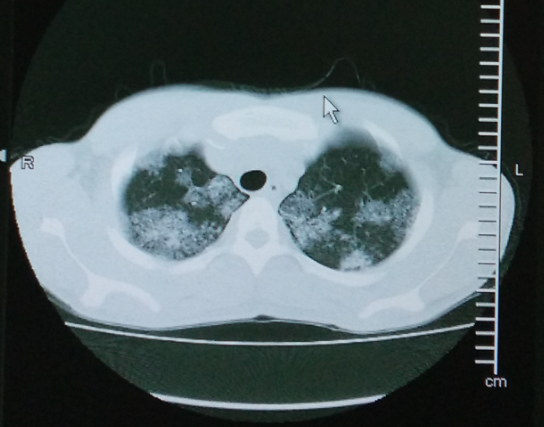

体查:T 36.8℃,BP 125/80mmHg,R 20次/分,P 80次/分。全身皮肤及粘膜未见瘀斑、黄染、苍白,全身浅表淋巴结未触及肿大。双肺活动度一致,叩诊清音,双肺呼吸音稍粗,未闻及明显干湿啰音。心腹查体无异常。生理反射存在,病理反射未引出。 辅查:尿酸UA 607umol/L ↑,红细胞沉降率(ESR,毛细管法) 25mm/h ↑;胸部增强CT:双肺多发多形性病变,以中上肺为主,右侧胸膜增厚、右侧胸腔多发包裹性积液,综合考虑为肺结核。支气管镜病理结果:右上叶后段送检直径0.2cm碎组织一堆,全埋制片。镜下:少量肺及支气管组织,其内见类上皮细胞团及多核巨细胞形成,伴小灶凝固性坏死,形态符合慢性肉芽肿性炎,考虑结核可能性大。刷片见支气管粘膜柱状上皮细胞,未见癌细胞。

随访:患者目前服用四联抗结核药,依从性较好,病情平稳,遂出院。 讨论:本病例患者无盗汗、低热、消瘦等典型结核症状,影像学结果也不是结核典型的部位和表现,单从病史及影像学依据,不能排除合并特殊病原菌感染及肺泡蛋白沉着症,所以安排患者进行支纤镜+病理活检以明确诊断。病理活检结果支持结核诊断,对患者进行四联抗结核治疗,同时嘱患者定期检查肝肾功能、血常规,定期复查胸部影像学。